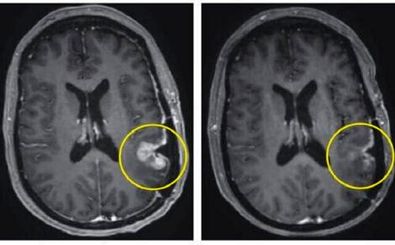

دانشمندان یک سامانه «هوش مصنوعی» را توسعه دادهاند که با استفاده از اسکنهای MRI متوالی، امکان بازگشت تومور مغزی در…